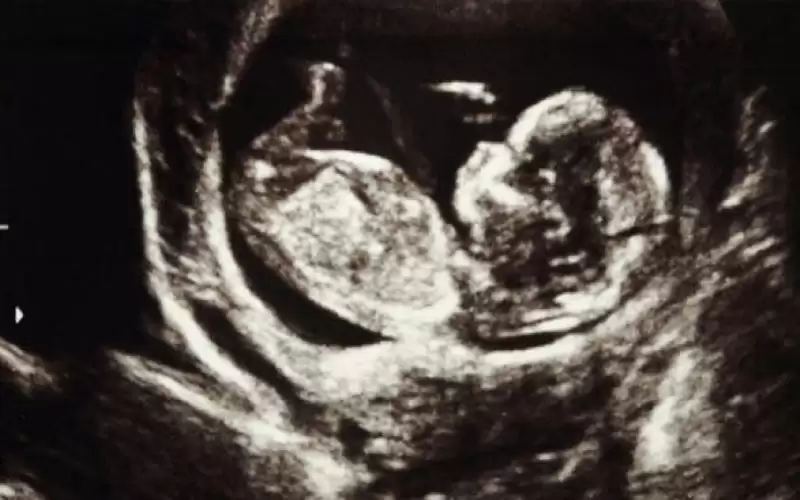

دراسة صادمة: التوتر أثناء الحمل يؤثر على صحة الطفل مدى الحياة